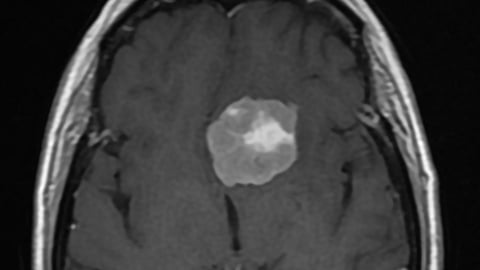

وتعود الحالة لمريضة، كانت تشتكي من صداع مزمن، ومشاكل في الرؤية؛ فقرر الفريق الطبي إخضاعها للفحوصات السريرية والإشعاعية التي كشفت عن ورم يضغط على منتصف الدماغ، ويحيط به شرايين دموية حساسة عدة، وأعصاب.